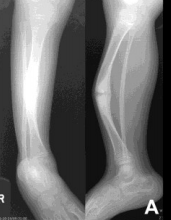

| What disease is this? What are the signs of this? | Osteogenesis imperfecta (“Brittle bone disease”) Diffuse cancellous osteopenia (coarse primary trabeculae), diminished tubular bone girth |

| What disease is this? | Osteogenesis Imperfecta |